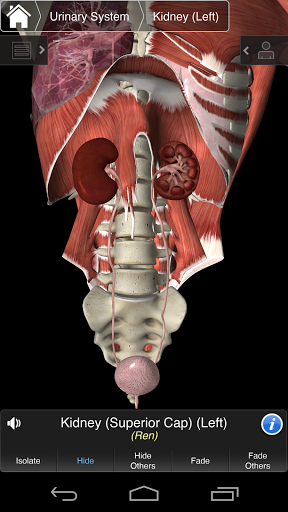

⁃Moczowy

---- Ponad 4000 bardzo szczegółowych struktur anatomicznych

---- Tryb wielokrotnego wyboru - Ukryj / Zniknij / Izoluj pojedyncze lub wiele struktur

---- Prawidłowa wymowa audio dla każdej struktury

---- nomenklatura łacińska dla każdej struktury anatomicznej